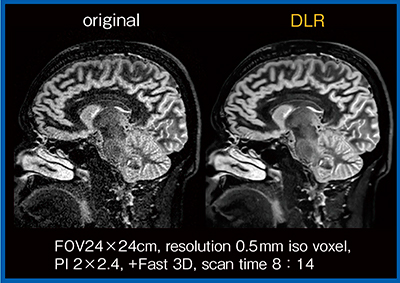

そこで,われわれは海馬のT2強調冠状断像を用いてDLRの検討を行った3)。定量評価では,高分解能T2強調画像と,加算回数の少ない画像,および少ない加算回数でDLRを適用した画像を比較したところ,DLRの画像では灰白質,白質,被殻,脳脊髄液のいずれにおいてもノイズが大幅に低減していた。視覚評価でも,DLRを適用した方が全体的に画質は良好であった。ただし,白質と被殻の境界や,海馬内の帯状の低信号は,DLRの強度が強すぎるとかえって不明瞭となることがわかった。また,オリジナル画像のコントラストが保持されていない場合は,DLRを適用しても病変や海馬内の微細構造物などの描出能は向上しなかった。さらに,ノイズを低減することでフローアーチファクトが目立つ場合も見られた。フローアーチファクトの低減には,3D-T2強調画像へのDLRの適用が有用かもしれない(図7:0.3mm iso voxel)。